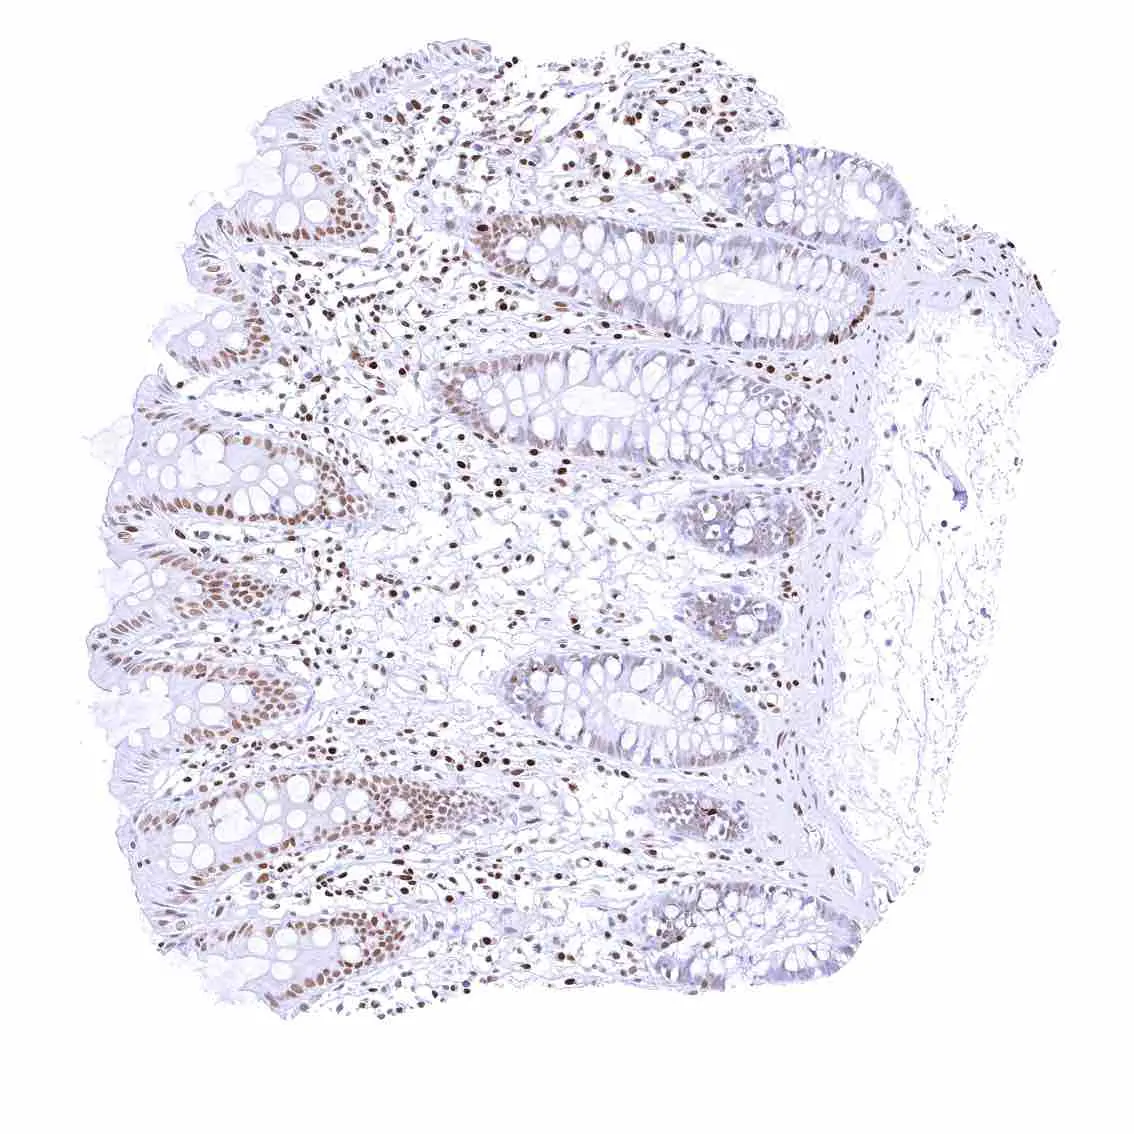

Colon descendens, mucosa

Duodenum, mucosa – Nuclear p27 positivity of a fraction of epithelial cells.

Ileum, mucosa – Nuclear p27 positivity of a fraction of epithelial cells.

Rectum, mucosa